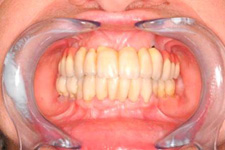

S těmito typy náhrad můžeme dosáhnout perfektní funkci, výbornou estetiku, fonetiku a současně zajistit u pacienta možnost dobré hygienickou péče a čištění, která je pro životnost implantátů velice důležitá.